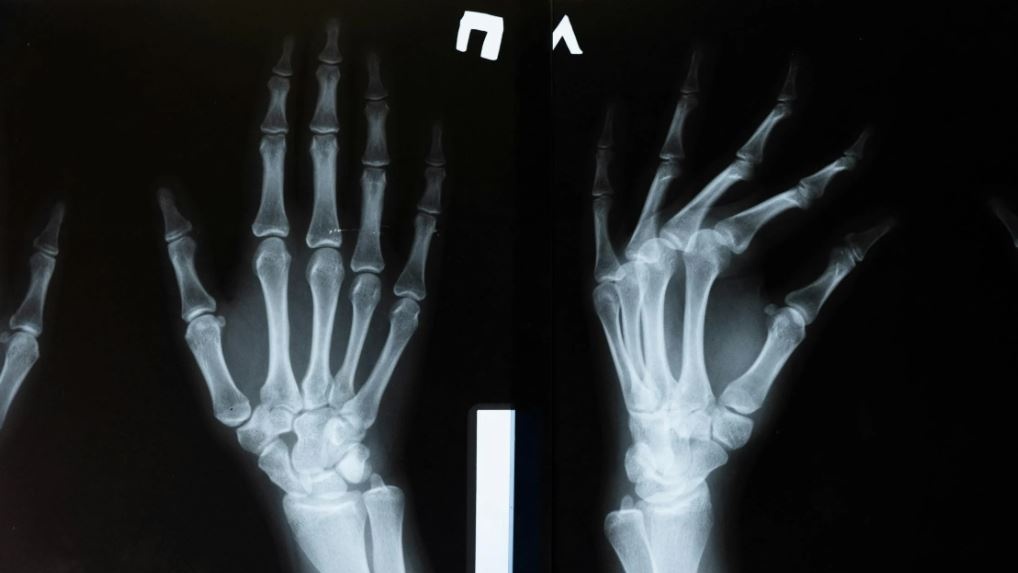

L'osteoporosi è una malattia cronica e progressiva che indebolisce le ossa e aumenta il rischio di fratture.

Per lo screening, Amgen raccomanda la densitometria ossea, un test che misura la densità minerale delle ossa e può valutare il rischio di fratture, diagnosticare la malattia e monitorare la risposta al trattamento.